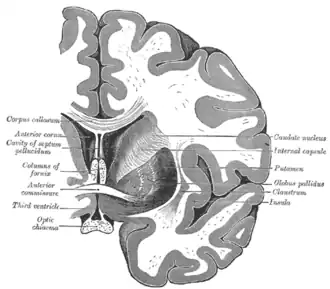

Ventricles of brain and basal ganglia. Superior view, horizontal section, deep dissection

Ventricles of brain and basal ganglia. Close-up of preceding image